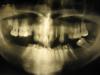

tchena Опубликовано 13 мая, 2010 Автор Поделиться Опубликовано 13 мая, 2010 А вот орто ее Ссылка на комментарий

Radar Опубликовано 14 мая, 2010 Поделиться Опубликовано 14 мая, 2010 Тут основная сложность с верхними молярами как их вколачивать или делать операцию.Остальное- завысить прикус на время ортодонтического лечения стянуть верхние зубы на низ бюгельный протез. Ссылка на комментарий

mojo83 Опубликовано 16 мая, 2010 Поделиться Опубликовано 16 мая, 2010 (изменено) Мое83, спасибо за ответ .Какой бы Вы предложили план без брекетов( тупо нет денег и взять негде).что касается протезной части- могу сделать сам практически даром в качестве благотворительности.Ммм... тупо ничего не делать. Нужно мнение ортодонта. И то на мой взгляд от ортодонтии только польза- похимичить с фронтом. Если просто заняться эксперементами аля родственник подруга , то можно попытаться увеличить клиничсекую высоту моляров. Попытатсья. Депульпировать. ЗАточить под убогие коронки. сделать сьёмник на нч. Это всё фантазии. Если реально то мне кажеться удаление 1.7,1.6,2.7,2.6-точно, с 1.5-скорее сохраниться,2.5 нужно думать. А там если бюджетно , то сьёмники. Хотя мне тоже интересно мнение коллег. В частности Fury Изменено 16 мая, 2010 пользователем mojo83 Ссылка на комментарий

Skip Опубликовано 18 мая, 2010 Поделиться Опубликовано 18 мая, 2010 Опять же старнно тема висит уже прилично, и никто ничего толком не сказал. Видимо куда интереснее обсуждать сдачи с зомгколичеством циркония на имплантантах, или концентрацию хлорки. Или никто ничего толком сказать не может? Варианты, предложенные лично Вами, вполне реалистичные, тут даже добавить нечего. Правда расставаться с молярами, я бы не спешил, т.к вдруг пац-ка разбогатеет (замужество, наследство, лотерея и т.п.) и сможет, в дальнейшем, позволить себе провести грамотную предортопедическую подготовку ... Скученность передних зубов на нижней челюсти, полностью исключает возможнось манипулирования её положением, с помощью сплинта например (full forward), поэтому функциональная ортопедия челюстей и ортодонтия, в данном случае, неизбежны.А то, что верхние моляры почти касаются беззубого гребня, то это только малая часть проблемы, видимая непосредственно на гипсовых моделях, сложенных вместе кое-как... ...основную проблему можно увидеть на ТРГ и в артикуляторе.... Ссылка на комментарий